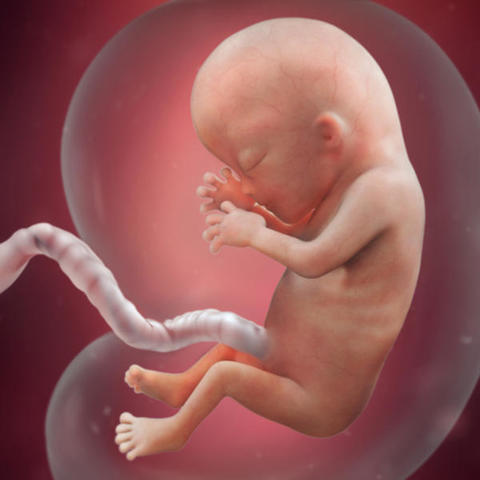

SEMANA 12

Comienzan a definirse sus uñas, el feto está totalmente formado, el sistema nervioso está madurando cada día, el latido de su corazón es perfectamente audible